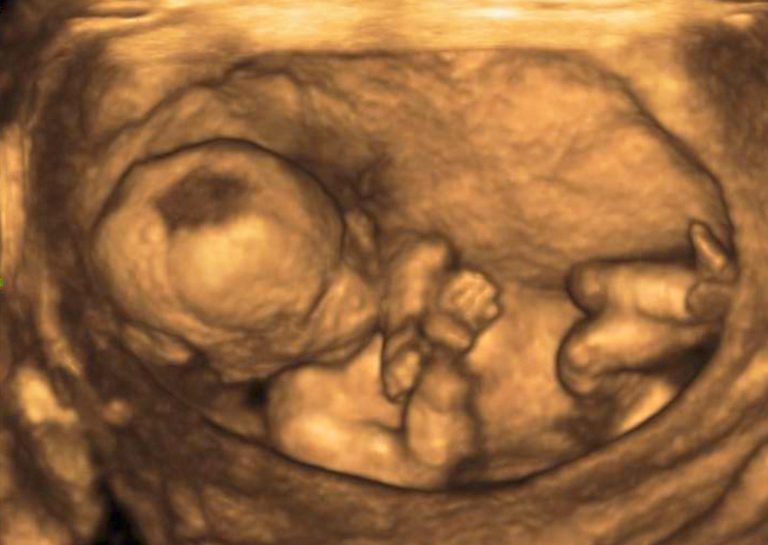

Zdravá těhotná žena, která v nemocnici Bulovka potratila, přišla podle CNN Prima News na běžnou kontrolu. Druhé ženě měli lékaři provést takzvanou kyretáž, která se provádí například při léčbě nemocné dělohy, ale lze tak i ukončit těhotenství.